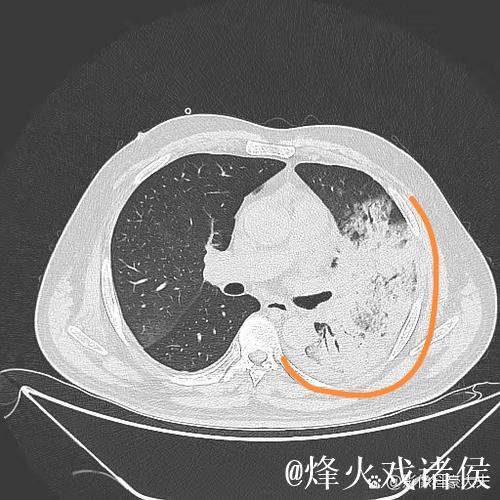

肺炎之所以让人恐惧,不仅因为它可能引发呼吸衰竭,甚至威胁生命,更因为它在短时间内剥夺了一个人对自己身体的信心。高烧、胸闷、呼吸困难,让人感到前所未有的无助。埃迪豪在住院期间,体验到那种“自己什么也做不了,只能依赖他人”的状态,这种深度依赖,让他对医护人员的信任不再停留在口头上,而是带着一种带有生死重量的感激。在无数次被抽血、做影像检查、调整药物方案的过程中,他感受到的是一种系统性的支撑机制从分诊、检查到治疗,再到随访,每一个环节都需要专业、协作和责任心。正是这种连贯的医护流程,让肺炎这样的急性疾病可以被及时识别和有效控制。

站在足球教练的视角看,医院就像一支分工精细的球队医生是“指挥官”,负责制定治疗策略;护士是“执行者”,在第一线完成护理操作;技师、药师、后勤人员则是“幕后战术群”,确保这一切顺畅运转。在一次肺炎治疗中,可能会涉及急诊、呼吸科、影像科、检验科、药房、病房护理团队,这些不同岗位间的衔接,就像是后防线、中场和锋线之间的传接配合。如果任何一个环节出现疏漏,患者的恢复过程就会被拖慢,甚至出现风险。埃迪豪在回顾自己的住院经历时,格外强调了对医护人员的尊重与感激,因为他看到,这支“生命球队”在没有聚光灯的地方,用专业和耐心守护着无数人的健康。与赛场不同的是,医院里的“失误”可能是生死之差,这让每一次加班、每一个夜班、每一份查房记录,都显得格外沉重而又值得敬佩。